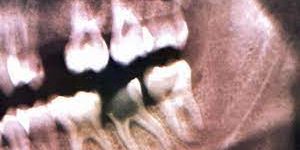

Археологические раскопки помогли понять: еще в эпоху неолита люди лечили и сверлили зубы. Были найдены останки людей с ровными отверстиями в зубах, которые были сделаны при жизни. А для пломбировки использовали субстанции, отдаленно напоминающие асфальт.

Хотя современных врачей эти методы лечения шокируют, в древности они были одними из самых прогрессивных. Так, зуб удаляли при помощи долота и молотка, предварительно его раскачивая и затем вынимая руками. Китайцы придумали прообраз современной зубной щетки, описали многие болезни десен и зубов, использовали лекарственные растения и создали первые пломбы из амальгамы. Первые варианты пломб были из расплавленного серебра, которым заливали кариозные полости.